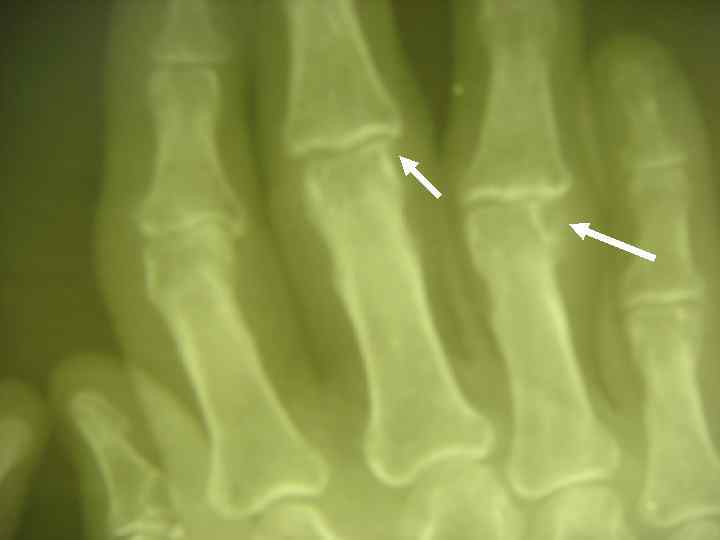

ДИАГНОСТИЧЕСКИЕ КРИТЕРИИ РА (АРА, 1987, 1998) l l l 5. НАЛИЧИЕ ПОДКОЖНЫХ УЗЛОВ В ОБЛАСТИ ЕСТЕСТВЕННЫХ КОСТНЫХ УТОЛЩЕНИЙ И РАЗГИБАТЕЛЬНЫХ ПОВЕРХНОСТЕЙ КОНЕЧНОСТЕЙ ИЛИ ПЕРИАРТИКУЛЯРНО (РЕВМАТОИДНЫЕ УЗЕЛКИ). 6. ОБНАРУЖЕНИЕ РЕВМАТОИДНОГО ФАКТОРА В СЫВОРОТКЕ КРОВИ ИЛИ СИНОВИАЛЬНОЙ ЖИДКОСТИ. 7. ТИПИЧНЫЕ РЕНТГЕНОЛОГИЧЕСКИЕ ИЗМЕНЕНИЯ: ОКОЛОСУСТАВНОЙ ОСТЕОПОРОЗ, ЭРОЗИВНЫЙ АРТРИТ.

R-ЛОГИЧЕСКИЕ СТАДИИ РА (STEINBROCKER, 1949) l СТАДИЯ I — ОКОЛОСУСТАВНОЙ ОСТЕОПОРОЗ БЕЗ l СТАДИЯ II — НЕЗНАЧИТЕЛЬНОЕ СУЖЕНИЕ l СТАДИЯ III — ЗНАЧИТЕЛЬНОЕ РАЗРУШЕНИЕ ХРЯЩА И l СТАДИЯ IV — ПРИЗНАКИ III СТАДИИ + АНКИЛОЗ ДЕСТРУКТИВНЫХ ИЗМЕНЕНИЙ. СУСТАВНОЙ ЩЕЛИ, ЕДИНИЧНЫЕ УЗУРЫ КОСТЕЙ. КОСТИ: ВЫРАЖЕННОЕ СУЖЕНИЕ СУСТАВНОЙ ЩЕЛИ, МНОЖЕСТВЕННЫЕ УЗУРЫ, ПОДВЫВИХИ, КОСТНЫЕ КИСТЫ.